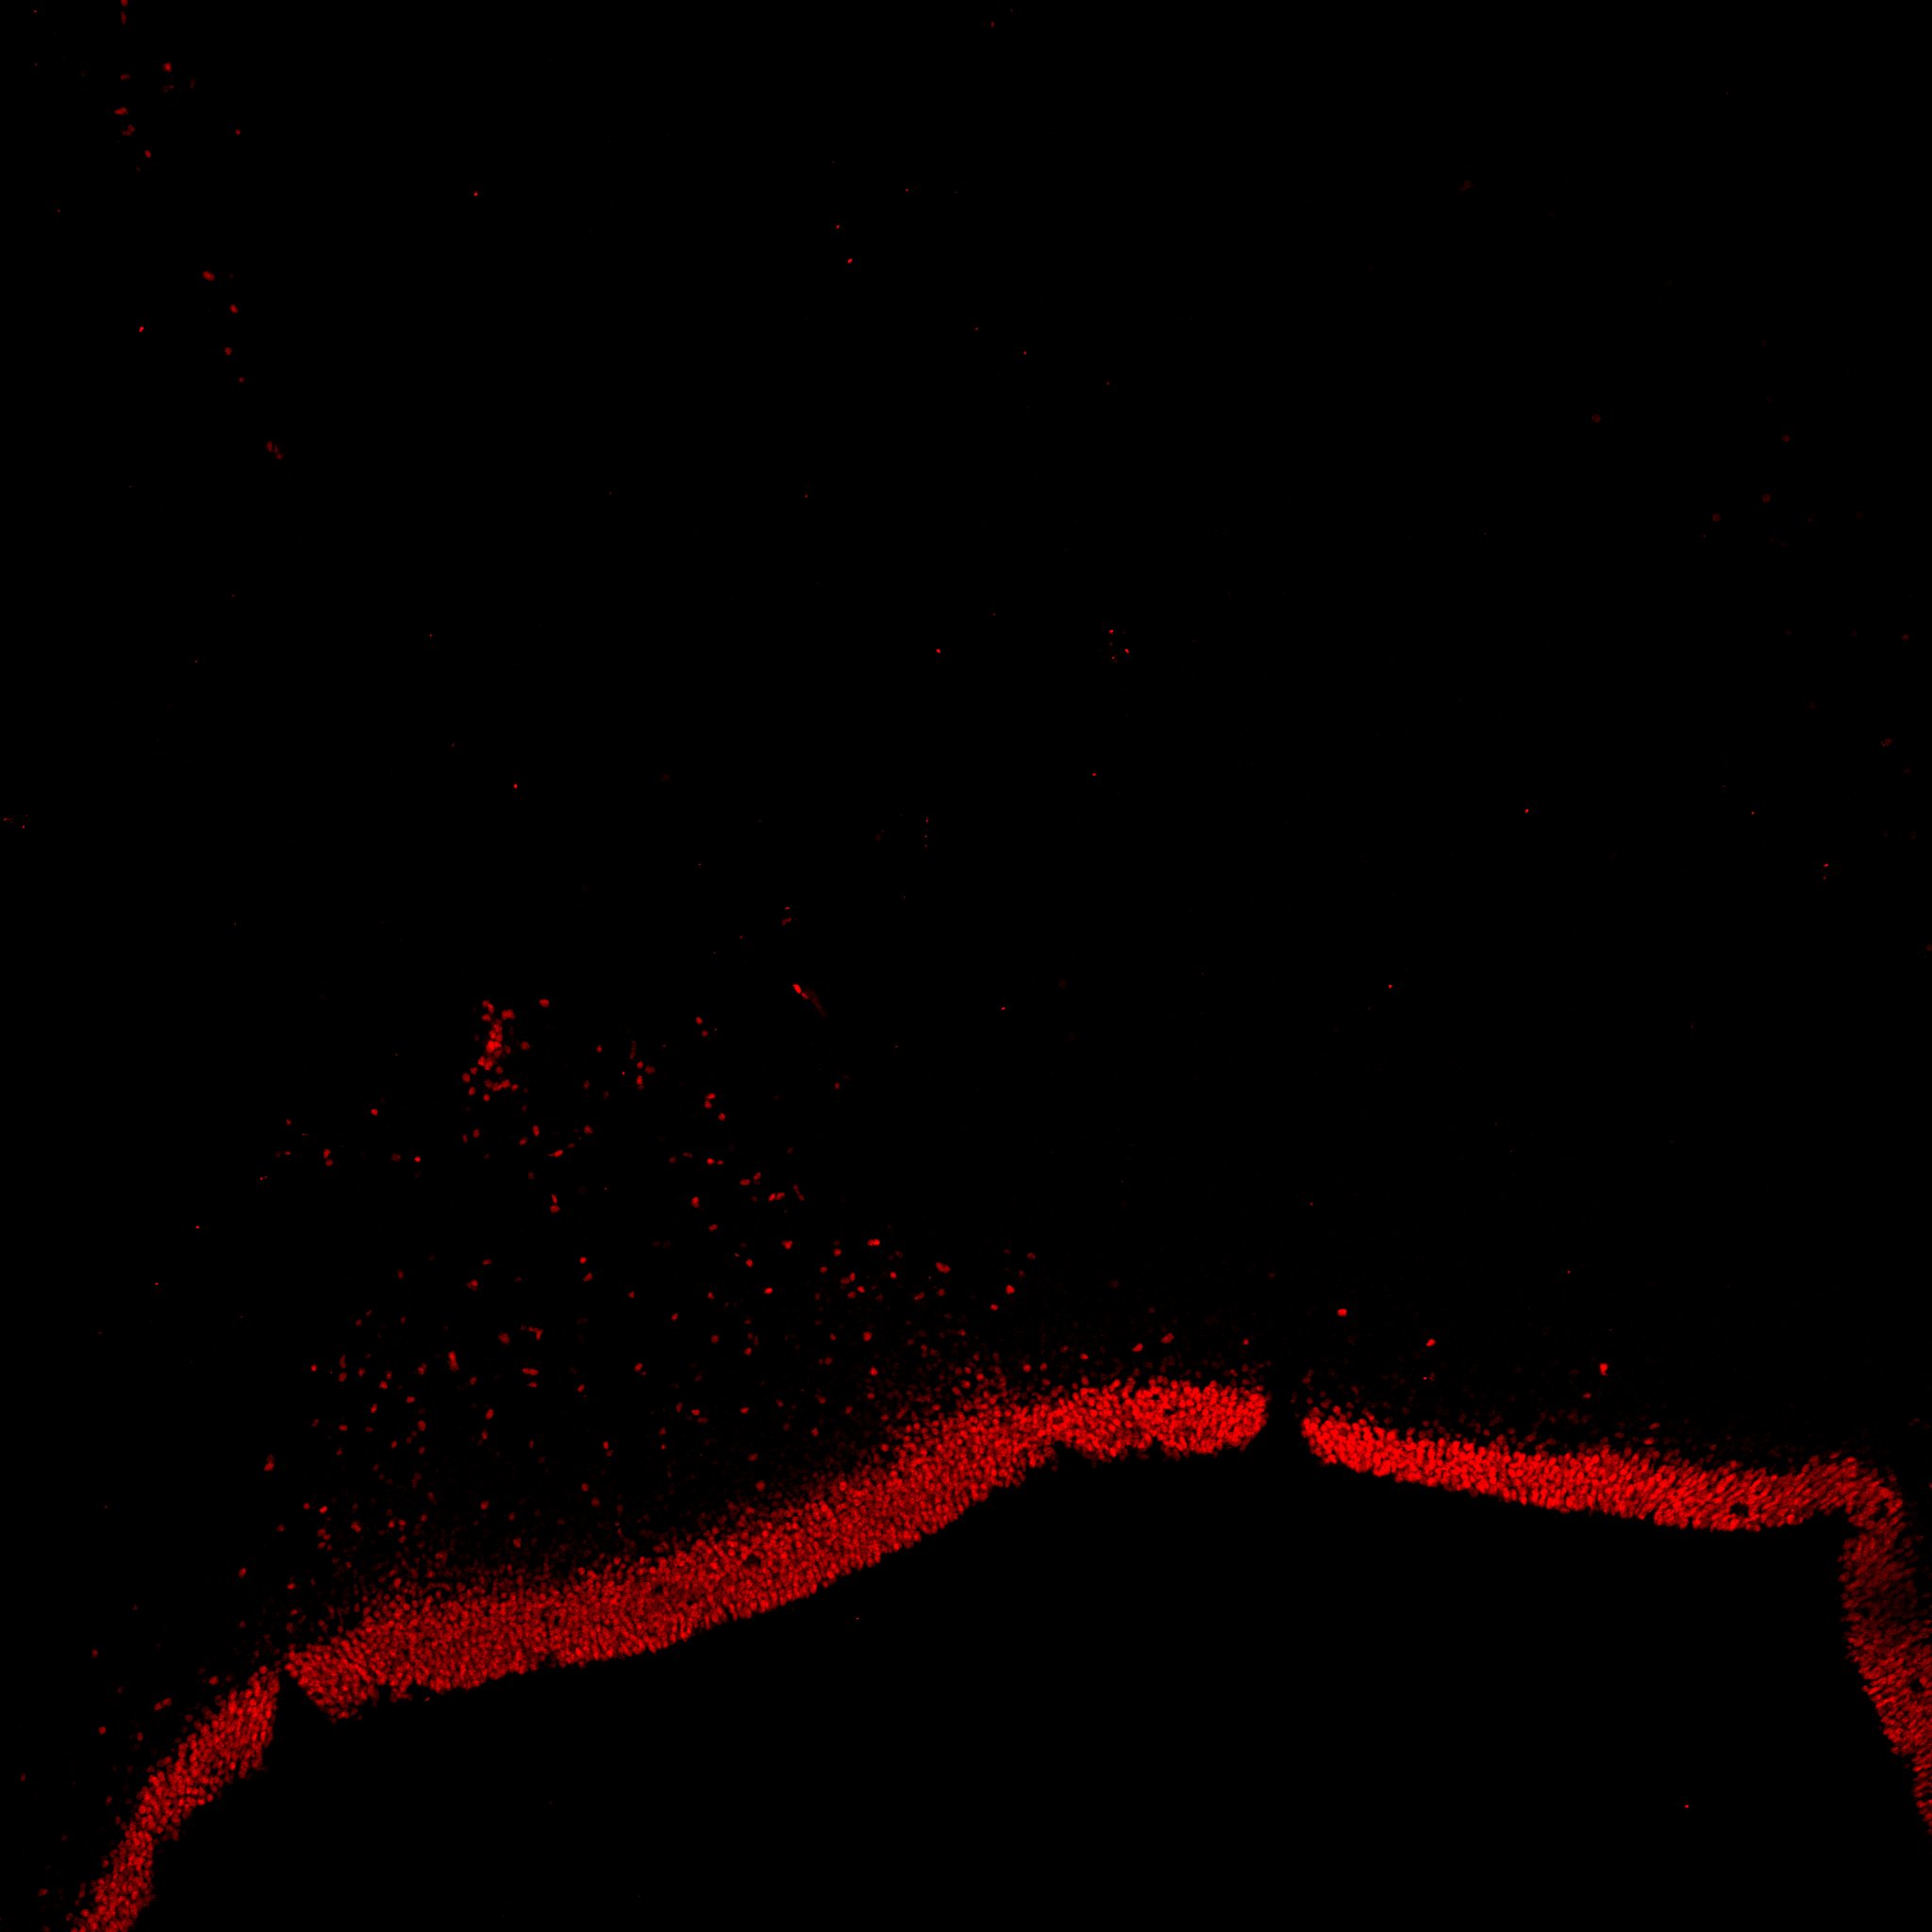

An anatomical analysis of the developing human midbrain from 6 post-conceptional weeks (PCW) to 22 PCW reveals increased tissue complexity, characterized by the emergence of dopaminergic nuclei, as highlighted by immunofluorescence analysis for tyrosine hydroxylase (TH).

TH

19PCW human midbrain